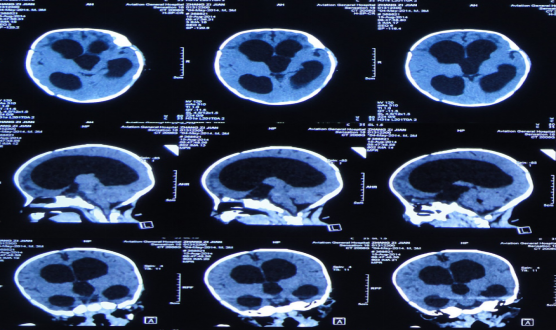

入院当天行脑室外引流术,引流的脑脊液淡黄色,细菌培养为无细菌,经引流第34天查头CT时,发现:右侧颞角孤立性扩大,其余脑室系统明显缩小。

治疗第42天行右侧侧脑室颞角引流术,第47天复查头CT: 右侧颞角及其余脑室系统大小正常,第63天行双侧脑室分流术,第74天出院,头围减小至39cm(活泼好动,恢复正常。